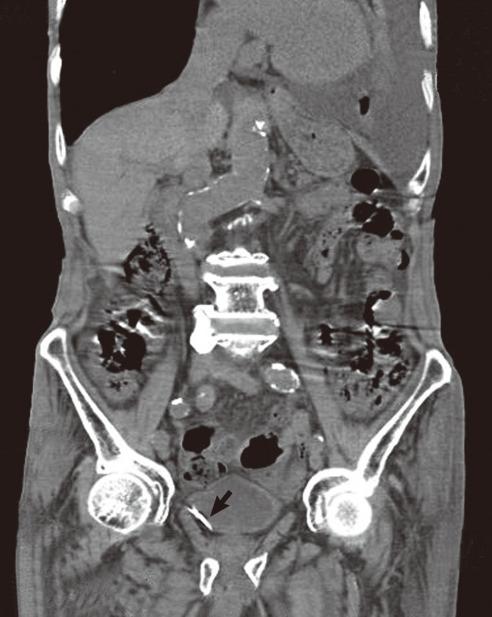

A foreign body near the bladder is rare. Although foreign bodies in the bladder can be easily found and removed by endoscopic transurethral removal, extravesical foreign bodies may require the use of an open or laparoscopic procedure. Here, we report a case of a patient complaining of frequency and urgency in whom an extravesical sewing needle was successfully removed by a laparoscopic approach. A 4.5 cm rusty sewing needle was found between the bladder and the left external iliac vessels and was removed through a 5 mm trocar port by use of endo forceps with no complications.

膀胱附近的异物较为罕见。虽然经尿道内镜取出术可以很容易地发现和取出膀胱内的异物,但对于膀胱外的异物可能需要采用开放或腹腔镜手术。在此,我们报告一例患者因尿频和尿急就诊,成功地采用腹腔镜方法取出了膀胱外的缝针。在膀胱和左侧髂外血管之间发现了一根 4.5 厘米长的生锈的缝针,通过使用内镜抓钳从 5 毫米的套管中取出,没有出现并发症。